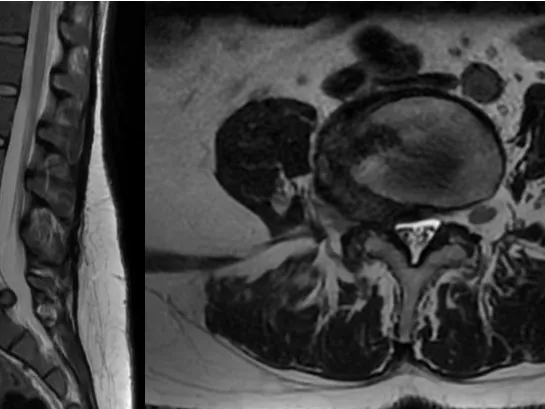

Improving MRI Reporting Accuracy for Degenerative Lumbar Spine

This online course aims to highlight the key areas of concern related to the lack of standardization in lumbar spine imaging, with a focus on terminology and interpretation discrepancies. Through the adoption of standardized interpretation guidelines, the course seeks to reduce subjectivity and improve accuracy in diagnosis and treatment through completing real-life cases on our Lumbar Spine Image Reporting Simulator and receiving immediate feedback from the experts who have designed the course.

The lumbar spine is a critical and complex anatomical region, and accurate imaging and diagnosis are crucial for effective management. However, inconsistencies in terminology and interpretation of lumbar spine imaging are common.

These discrepancies often lead to miscommunication between professionals, resulting in repeat imaging, additional consultations, and increased healthcare costs. Chronic lumbar spine conditions are a leading cause of disability and work absenteeism, affecting both individual livelihoods and overall economic productivity.

This fellowship will combine lectures from experienced lumbar spine experts, with reporting on real-life cases, participants will review a number of cases for each of the indicated topics.

• Accurately describe the MRI findings using standardized terminology. Develop consistency in reporting to improve interdisciplinary communication.

• Identify central canal stenosis on MRI and apply grading criteria. Differentiate between central and lateral recess stenosis and their impact on nerve roots.

• Identify foraminal stenosis on MRI and its impact on exiting nerve roots.

• Evaluate and differentiate the various types of spinal disc herniations on MRI, including protrusions, extrusions, and sequestrations, using a standardized classification system.

• Define spondylolisthesis and recognize its subtypes on MRI.

• Comprehend the principles of structured MRI reporting for the lumbar spine, including critical elements such as: alignment, stenosis, disc pathology, nerve root involvement